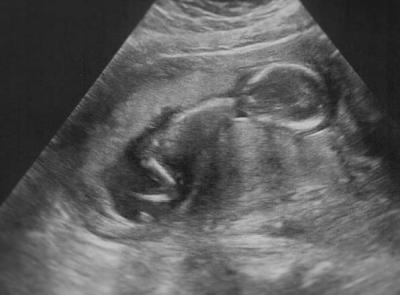

dass ich mein letztes US Bild noch gar nicht eingestellt habe. Leider sieht man das Kleine nur von hinten, den Kopf auf die Plazenta platziert, als wäre es ein Kuschelkissen. Donnerstag hab ich dann meinen nächsten FA Termin. Ich bin gespannt, ob das Kleine sich weiter verstecken will.

Das ja mal nen außergewöhnliches Foto... Süß...